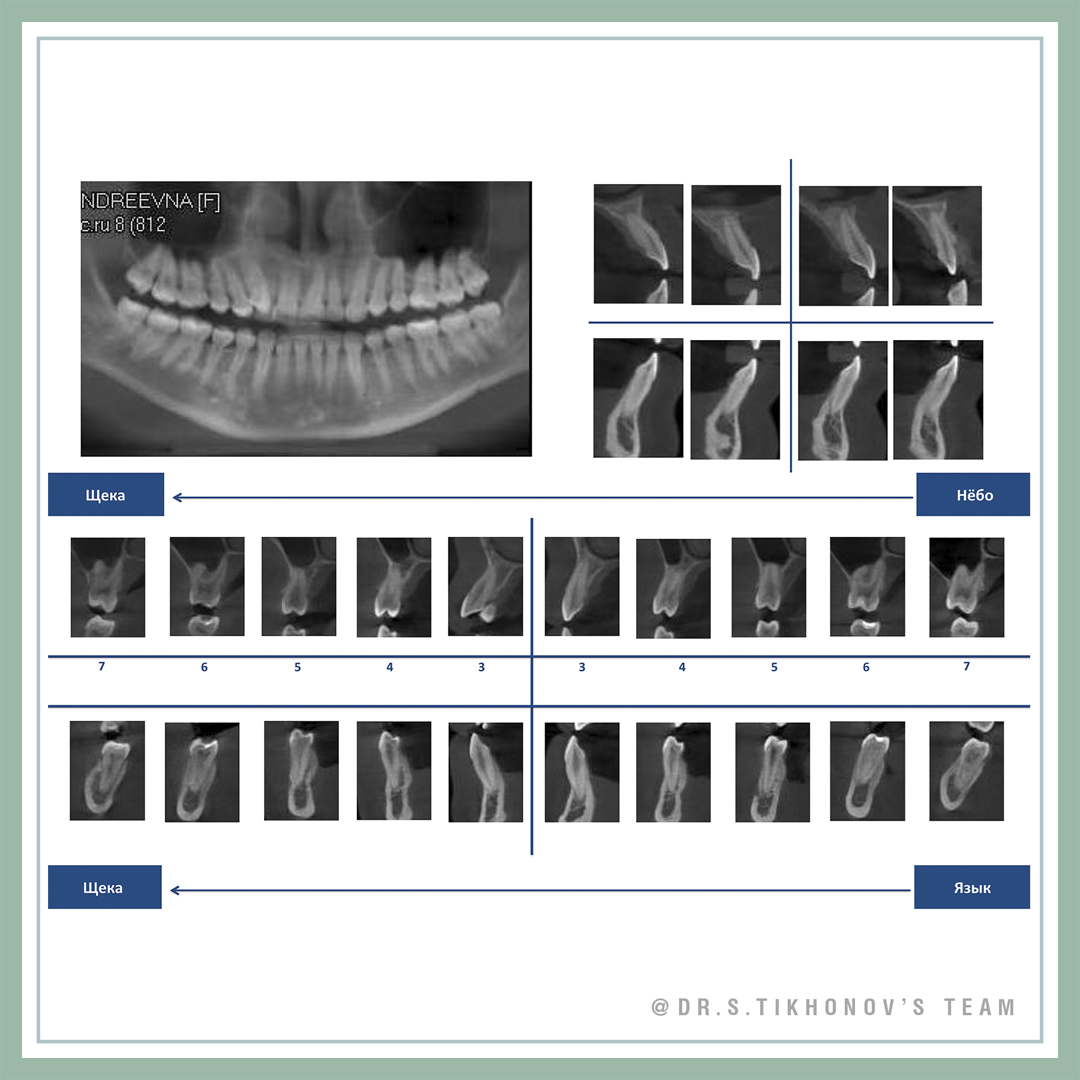

Конечно, я пару раз показывал ее на семинарах, но не все были, не все помнят. Взрослая, с мезиальным прикусом, беспокоит клык и обратное перекрытие, на лицевые признаки жалоб нет. Подробнее диагностическая информация на слайдах.

Сложность тут не только в мезиальном прикусе и перекрытии, но и в очень сильном дефиците места для 13. В Школе мы обсуждаем 5 способов создания места. Интересно, какие подходят здесь?

28 y.o., skeletal class 3, chief complaints: 13, anterior cross bite, facial appearance is ok! Please, share your Tx options in comments! Don’t be shy! This is the training account!